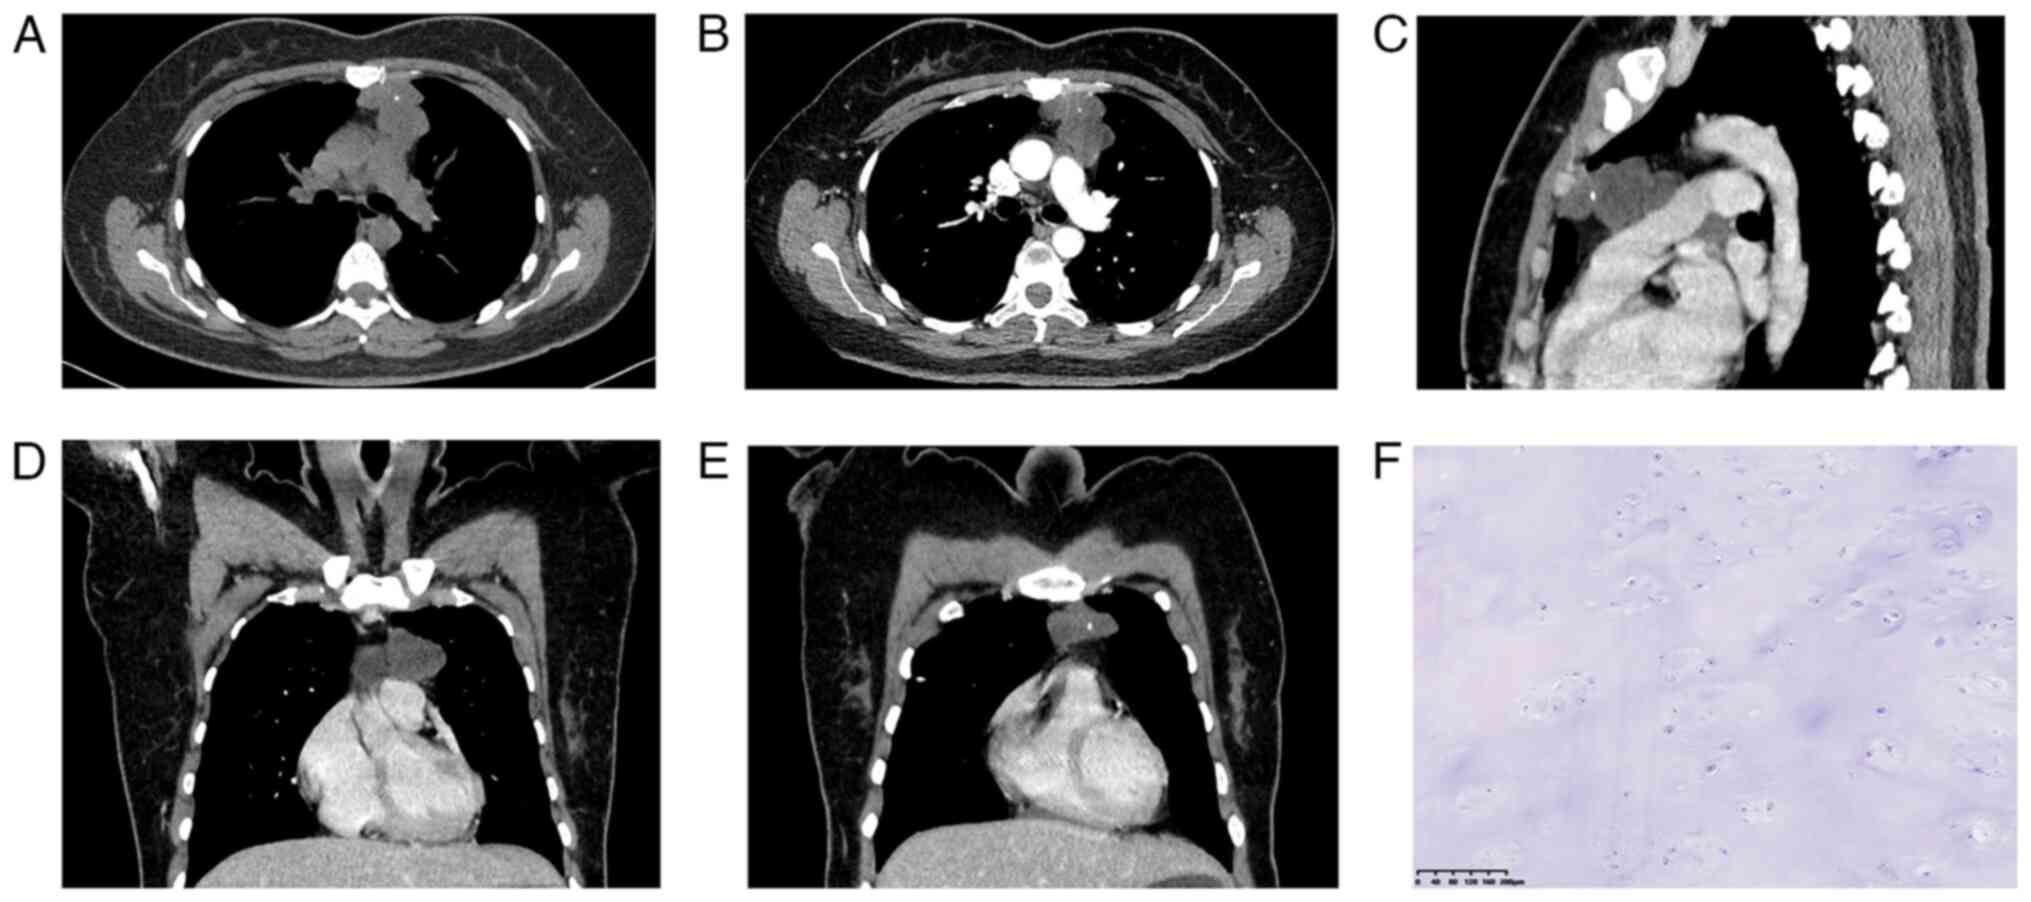

A 36-year-old Chinese female presented with an incidental finding of an anterior mediastinal mass during a routine health examination at a local hospital in June 2020. The patient was asymptomatic at the time of discovery, with no history of chest pain, dyspnea or other respiratory symptoms. Computed tomography (CT) revealed a lobulated, low-density mass measuring ~4.7x4.0 cm in the anterior mediastinum. Punctate calcifications were observed within the lesion and no significant enhancement was noted on contrast-enhanced imaging (Fig. 1A-E). The mass did not exhibit any signs of invasion into surrounding structures and there was no evidence of associated lymphadenopathy. Given the benign imaging characteristics, the patient underwent a median sternotomy for surgical resection of the mass. Intraoperatively, the tumor was well-encapsulated and easily separable from adjacent mediastinal structures (Fig. 1). The fully resected mass was confirmed the diagnosis of a soft tissue chondroma. The tumor was composed of mature hyaline cartilage with focal calcified areas and did not exhibit any signs of malignancy based on hematoxylin and eosin staining (Fig. 1F).